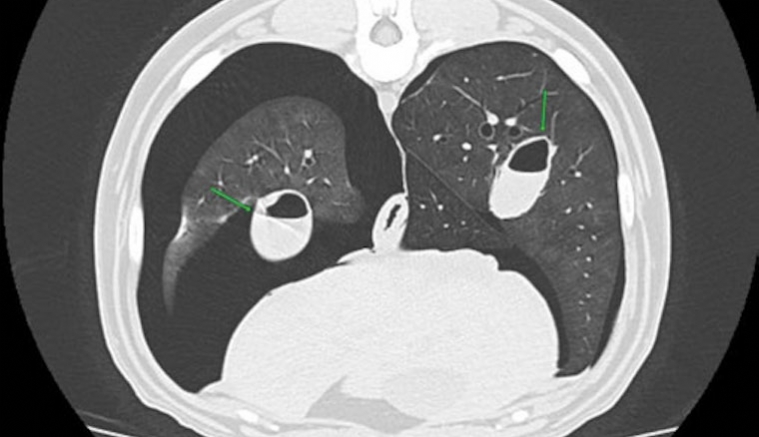

Pleurodèse par injection intrapleurale de sang dans la gestion d'un pneumothorax persistant

La pleurodèse est une technique rapide, facile et peu couteuse utilisée en médecine humaine et en médecine vétérinaire dans la gestion des pneumothorax persistants. Cet article abordera le principe de la pleurodèse au sang, ses indications et sa réalisati...